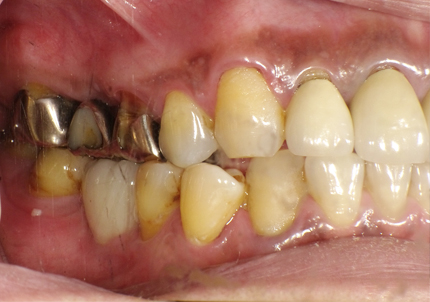

患者:Y.S 様

初診日 :2018年10月

主訴 :上顎前歯部審美障害、臼歯部補綴治療

1.初診時口腔内写真(2018年10月)